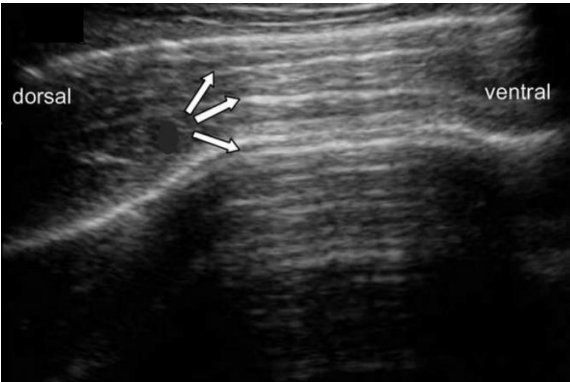

Analise a imagem a seguir.

Nessa imagem de um exame ultrassonográfico, qual é o artefato de imagem indicado pelas setas?

No exame ultrassonográfico, o sombreamento acústico é causado pela presença de quais compostos?